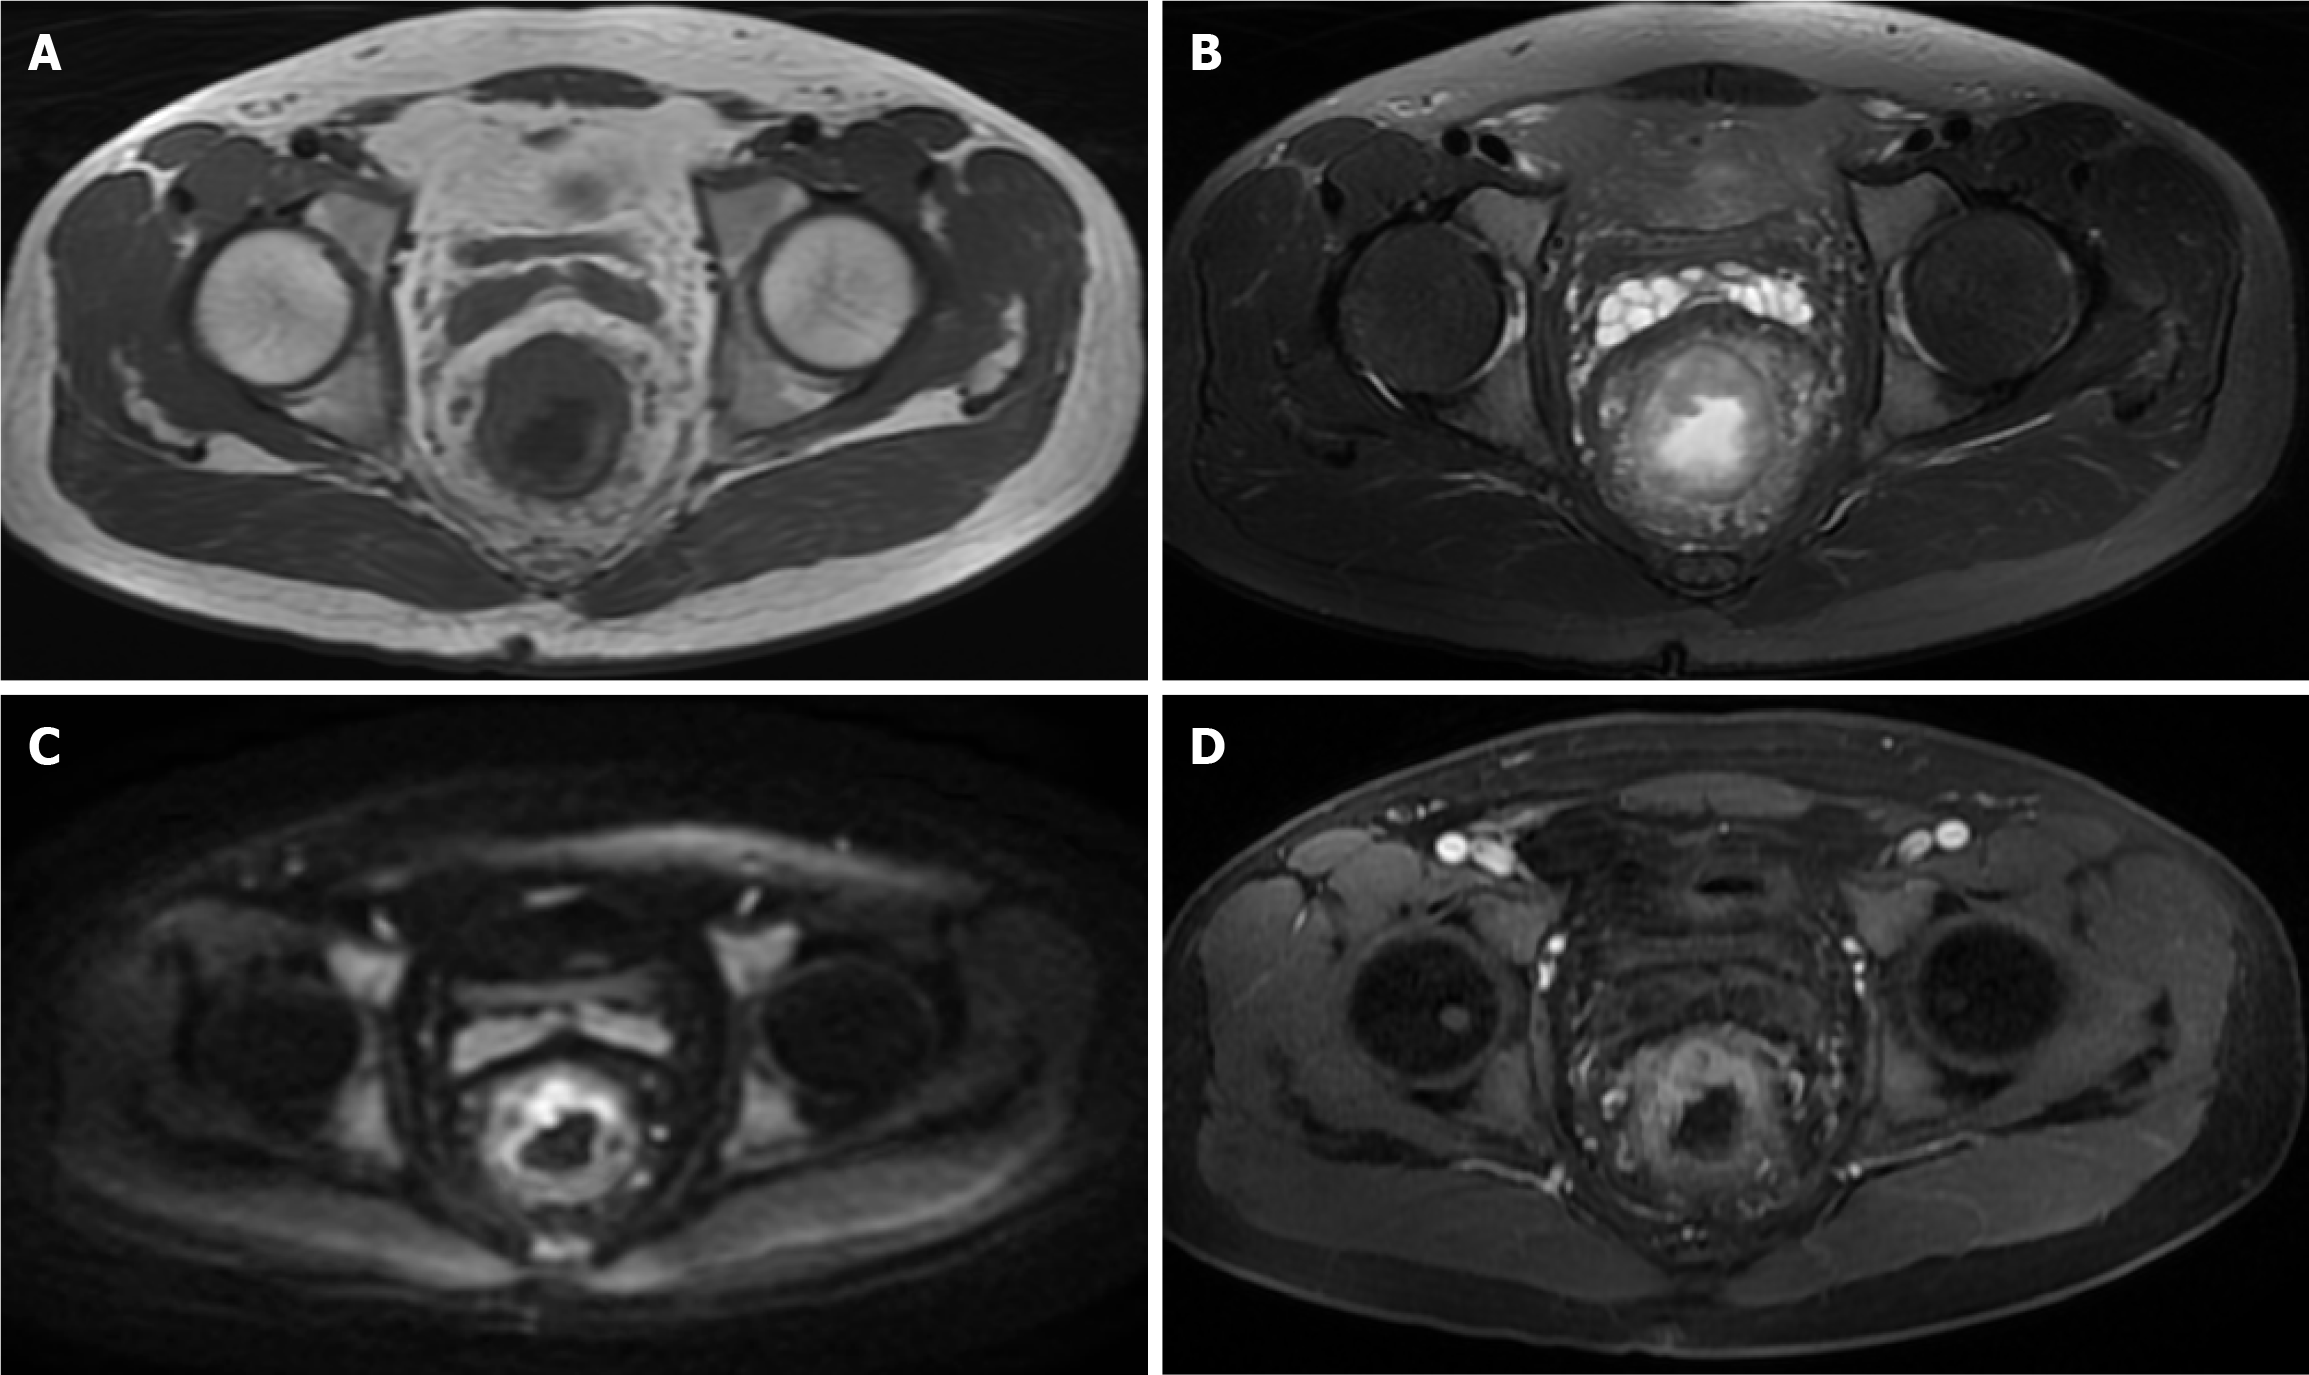

DCE-MRI examination: All patients underwent DCE-MRI examinations using the GE SIGNA Voyager 1.5T MRI system with a body phased-array coil. Prior to the examination, patients fasted for 4 hours, emptied intestinal gas, and were scanned in the supine position. Routine scanning included axial T1 weighted image, T2 weighted image, and sagittal T2 weighted image sequences. Dynamic contrast-enhanced scanning was performed using the liver acquisition with volume acceleration sequence, with scanning carried out at the end of expiration while the patient held their breath. The scan parameters were set as follows: Repetition time 3.5 ms, echo time 1.3 ms, flip angle 15°, slice thickness 3 mm, no gap, matrix 256 × 192, field of view 260 mm × 195 mm. Gadoteric acid contrast agent (0.1 mmol/kg) was injected via the antecubital vein at a rate of 3.0 mL/second, followed by a 20 mL saline flush. Three-dimensional volumetric scans were performed, acquiring baseline images before contrast injection and continuous acquisition of 10 time points post-injection, each with a scan time of 12 seconds. Images were processed using the workstation and the accompanying DCE-MRI post-processing software to obtain the time-signal intensity curves and quantitative perfusion parameters for the region of interest (ROI). The ROI selection avoided areas of necrosis, cystic changes, and large vessels. All image acquisition and analysis strictly followed standard operating procedures to ensure data accuracy and reproducibility (Figure 2).